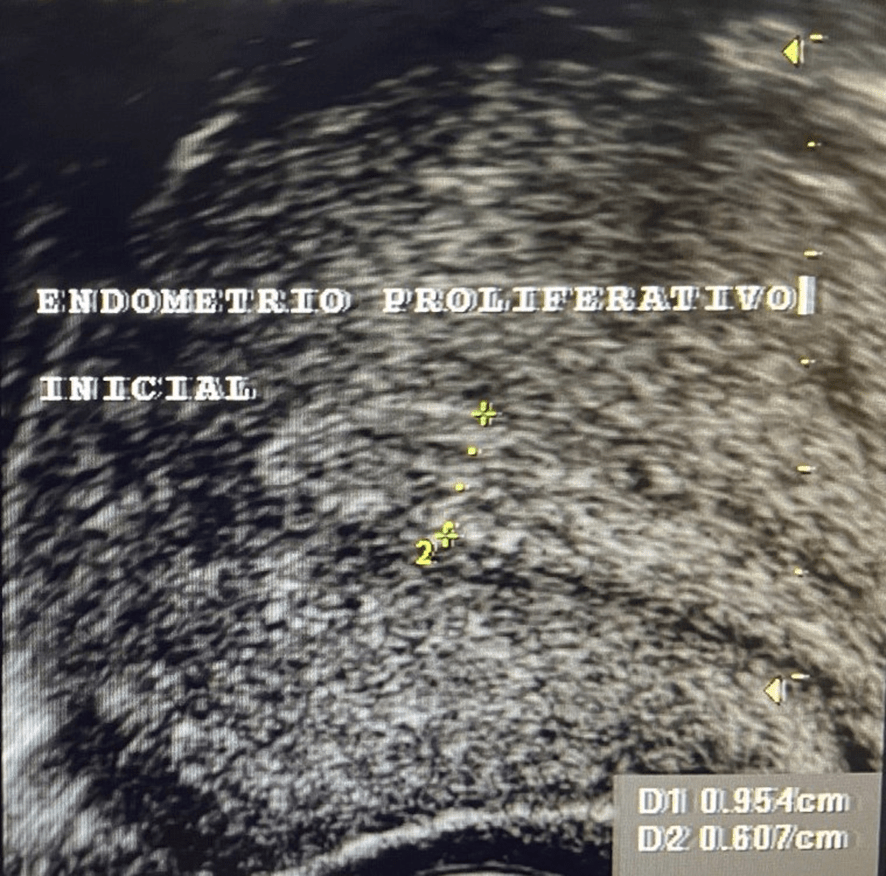

Una vez que el folículo maduro se ha roto -ha estallado- y se ha expulsado el óvulo que contenía (ovulación) la capsula del folículo adquiere un aspecto rugoso, grueso e irregular al que llamamos “cuerpo lúteo”. En su interior, frecuentemente, se produce un acúmulo de sangre por lo que también se le conoce como cuerpo lúteo hemorrágico.

Además de estrógenos, este cuerpo lúteo empieza a segregar una hormona llamada Progesterona; la cual, es la causante de que el endometrio- que antes de la ovulación era proliferativo y con sus tres capas bien definidas- se transforme en un endometrio grueso, espeso e irregular. Se le conoce como “endometrio secretor”.

Sumando los 14 días que suele durar la fase folicular o proliferativa a los otros 14 que dura la fase lútea, luteínica o secretora, nos dan los 28 días que suele durar el ciclo menstrual.